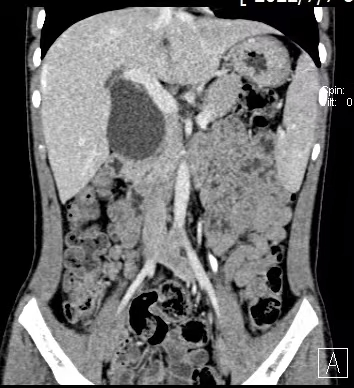

先天性胆总管囊肿是一种较少见但危害严重的胆道先天畸形,可能导致胆汁淤积、反复胆管炎、胰腺炎,并有远期癌变风险。根治性切除囊肿并重建胆道是唯一有效的治疗方法。然而,幼儿腹腔空间小、组织器官娇嫩、血管胆管纤细,手术操作犹如“精雕细琢”,对主刀医生的技术、经验以及整个麻醉、护理团队的配合都提出了极高要求。

术中,手术团队在放大数倍的高清视野下,精细分离、完整切除了巨大的胆总管囊肿,并成功实施了“肝总管-空肠Roux-en-Y吻合术”,在彻底去除病灶的同时,为患儿建立了通畅、符合生理的胆汁引流通道。整个手术过程如行云流水,出血量极少,最大程度保护了周围稚嫩的组织结构。